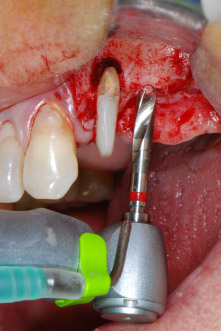

IImplant beds were prepared at sites 25 and 26 with rotary instruments, used in a contra-angle handpiece with a 20 : 1 transmission ratio with an updated powerful implant motor (Implantmed, W&H) (Fig. 8).